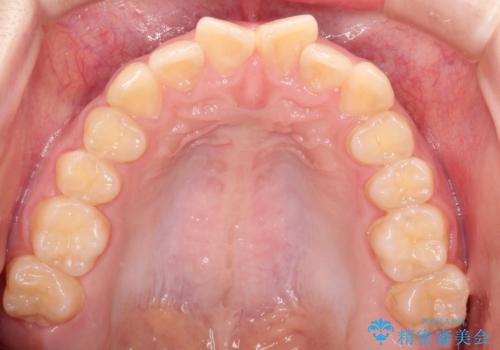

上下の前歯のガタガタを目立たず治したい インビザラインによる見えない矯正

- 上下の前歯のガタガタを治したいとのことで来院されました。

上下の歯と歯の間をわずかに削り、並べる計画としました。

上下の正中が一致していませんが、受験を控えているためご本人の希望もあり、いったん終了とさせていただきました。